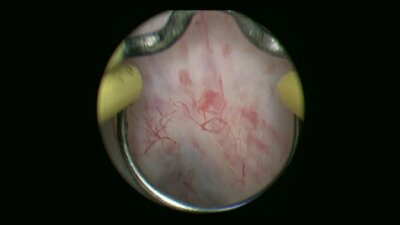

Операции на простате